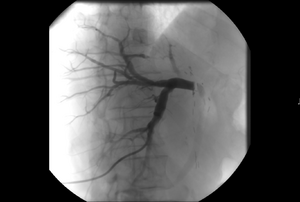

- Angiography: Sometimes referred to as traditional angiography, catheter angiography or digital subtraction angiography (DSA). A small needle is inserted into a blood vessel, then exchanged for a catheter over a wire. The catheter is directed at the vessel to be studied, and contrast is directly injected to evaluate the lumen under video X-ray. This is an older technique than modern CT angiography or MR angiography, but provides unique advantages. With a catheter in place, provocative maneuvers can be performed such as breath holds or instillation of vasodilators, to evaluate a patient's blood flow dynamically. This can reproduce symptoms and identify functional abnormalities in a vessel that a static CT or MR imaging cannot.[84][85] Angiography provides the basis for all endovascular therapy.

- Balloon angiography: The foundational IR procedure. Small balloons can be inflated inside a narrowed vessel to open it. These can then be safely deflated and removed. Some balloons have a specialized surface material, such as fine razor blades ("cutting balloons") to crack the plaque or instill a coating of medicine ("drug-coated balloon") that keeps the vessel open longer.